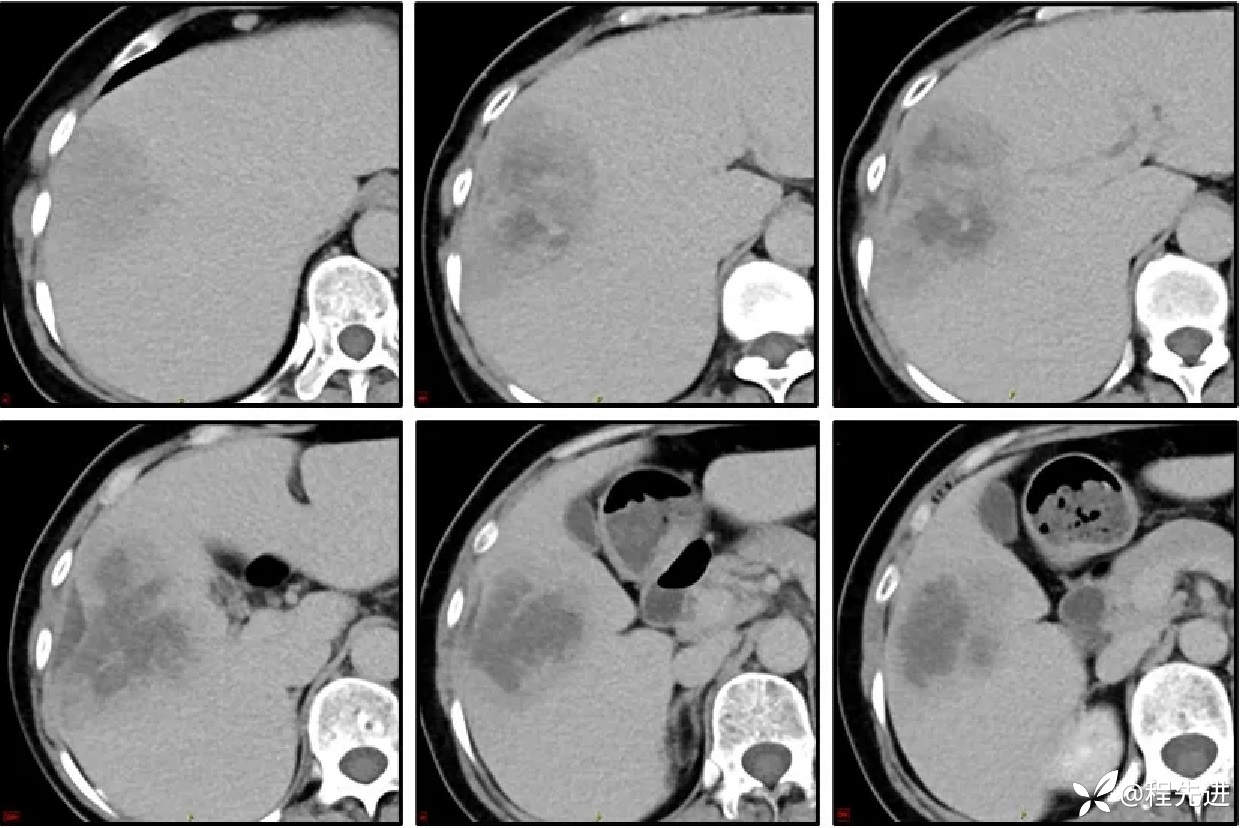

CT增强,3期: